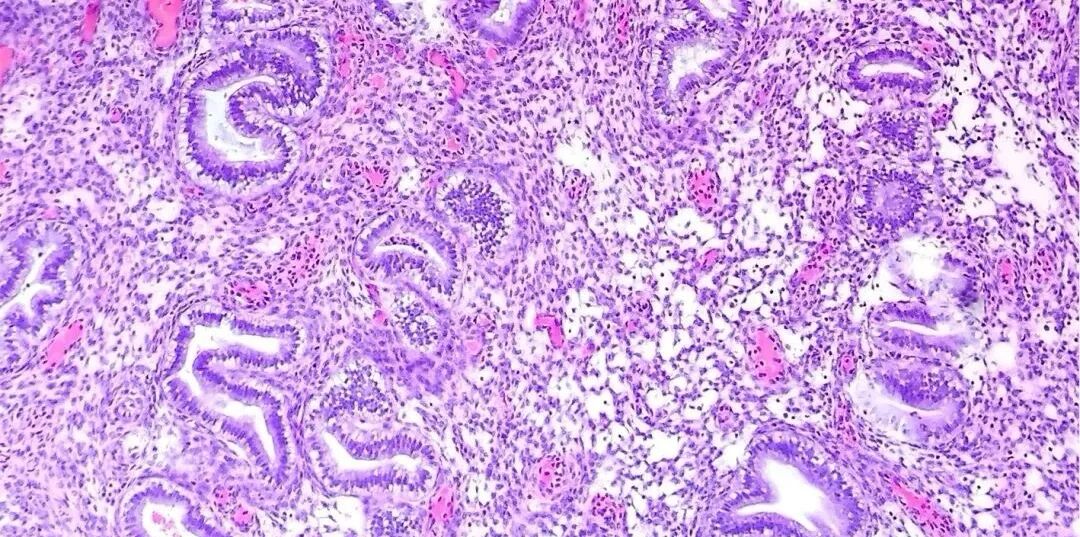

输卵管功能变化

即使没有怀孕史、没有人流手术经历,随着年龄增长,输卵管也可能自然不通。这是因为:

· 感染性疾病(如盆腔炎)的发生率随年龄增加

· 输卵管蠕动功能逐渐减弱

· 内膜容受性下降